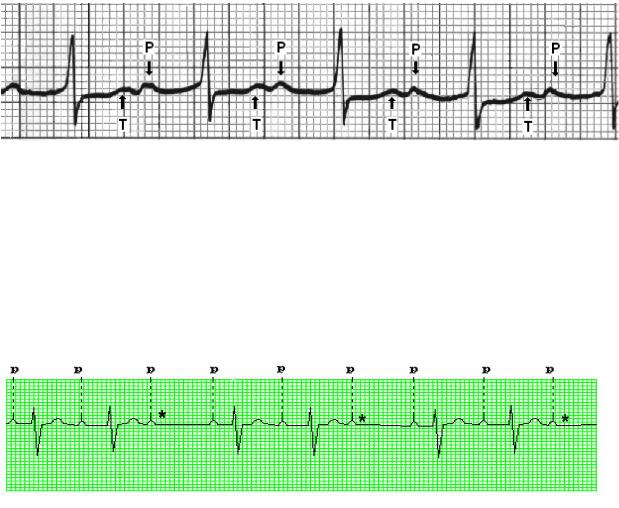

Неполная АВ-блокада II степени бывает двух типов. При типе Мёбитц 1 (рис. 2.3) происходит постепенное от цикла к циклу удлинение интервала PQ вплоть до полной блокады очередного импульса, когда после зубца Р отсутствует желудочковый комплекс QRS. После паузы проведение восстанавливается и события повторяются. Каждый такой период от первого сердечного цикла после паузы до первого сердечного цикла после следующей паузы называется периодом Самойлова – Венкебаха. Такая блокада обычно является функциональной.

Рис. 2.3. АВ-блокада 2-й степени типа Мёбитц 1 (3:2): наблюдается постепенное удлинение интервала PQ вплоть до выпадения очередного комплекса QRS (звездочка), затем укорочение PQ. В периоде Самойлова – Венкебаха три сокращения предсердий (3 зубца Р) и два сокращения желудочков (2 комплекса QRS)